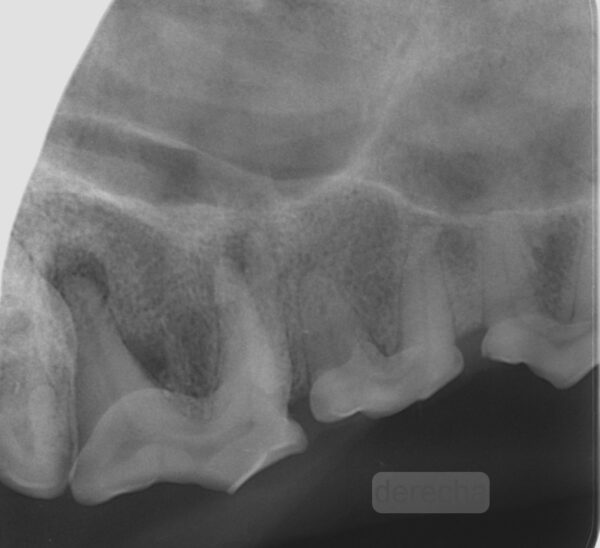

Caries

La caries es una desmineralización del diente como consecuencia de los ácidos producidos por la fermentación de los carbohidratos por parte de la placa bacteriana. Esta desmineralización y destrucción del esmalte y la dentina ocasionan pérdida de la densidad en la zona afectada del diente (imagen 12).

Aunque la caries puede afectar a cualquier diente, en la mayoría de las ocasiones, en los perros, aparece de forma más frecuente en la superficie oclusal de la cara distal del primer molar mandibular y del primer molar maxilar. Estos dientes son particularmente propensos a la caries debido a sus características anatómicas (presencia de fosas y surcos).

A nivel radiológico, la lesión se manifiesta como una imagen radiolúcida de bordes irregulares. La línea delimitante de la lesión dependerá de la etapa del proceso, en un principio se trata de una zona radiolúcida que se extiende desde la superficie dental del esmalte profundizando hacia la dentina y, una vez que la caries alcanza la dentina, la lesión se extiende rápidamente bajo el esmalte, convirtiéndose en mucho más grande de lo que sospechamos por inspección visual.

La profundidad de la lesión, su proximidad a la pulpa, así como las posibles lesiones periapicales, solo pueden valorarse mediante radiografía.